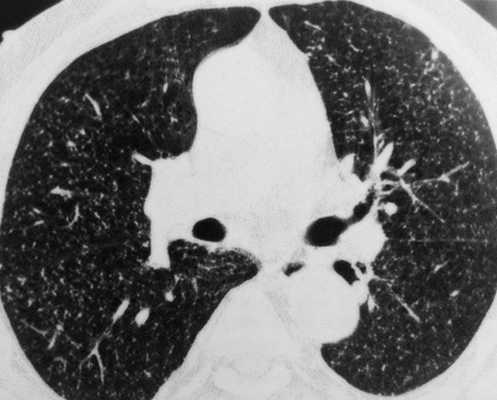

Очаговые изменения на КТ легких, подозрительные на туберкулезное поражение (выделено красным)

Туберкулез поражает пациентов любого возраста и пола, легкие вовлекаются в процесс наиболее часто. Болезнь считают социально опасной, так как при несвоевременной диагностике открытой формы (выделение микобактерий в окружающую среду при кашле) высок риск инфицирования окружающих людей. КТ органов грудной клетки при туберкулезе назначают в следующих ситуациях:

Туберкулез легких на КТ (множественные очаги)